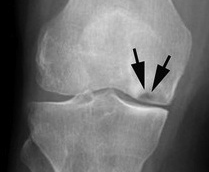

Εκφύλιση του γόνατος μπορεί επίσης να προκληθεί από μια κατάσταση που αναφέρεται ως οστεοχονδρίτιδα. Αυτή κυρίως προσβάλλει νέους ενήλικες και εφήβους. Σε αυτή το υποχόνδριο οστό σε ορισμένα σημεία (κυρίως στους έσω μηριαίους κονδύλους) γίνεται μαλακό και χάνει την συνοχή του με το υπόλοιπο οστό. Σε προχωρημένα στάδια αυτό το τμήμα του οστού μπορεί να αποκολληθεί και να λειτούργει σαν ελεύθερο σώμα εντός της άρθρωσης. Αυτά τα ελευθέρα σώματα ποικίλουν σε μέγεθος και μπορούν να προκαλέσουν αστάθεια, πόνο ή μηχανικό block.

Για λόγους που δεν είναι απόλυτα τεκμηριωμένοι (π.χ. λήψη κορτιζόνης σε μεγάλες δόσεις, δρεπανοκυτταρική αναιμία κλπ) ένα τμήμα του μηριαίου η του κνημιαίου κονδύλου μπορεί να υποστεί έμφραγμα που οδηγεί σε ισχαιμική νέκρωση. Το αποτέλεσμα είναι το νεκρωμένο υποχόνδριο οστό να μην μπορεί να υποστηρίξει τον υπερκείμενο αρθρικό χόνδρο, να υποχωρεί και ο κόνδυλος να χάνει το σχήμα του.